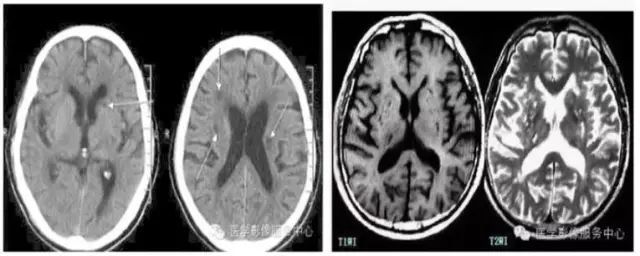

1. 把“血管周围间隙”误认为腔梗

文章插图

血管周围间隙 , 在影像上 , 比如 CT表现为两种情况: 圆形 , 周围非常光滑界限清楚; 线形 , 灶小 , 1.9 × 0.9 毫米 , 一般病灶小于 2 × 1毫米;总的来说形态不行 , 大小也不同 。

腔隙性脑梗死呈楔形、三角形或月牙形 , 平均大小 3.0 × 1.6 毫米 , 60% 大于 2 × 2 毫米 , 边界模糊 。 注意 , 脑干上3 × 2 毫米以上的病灶 , 腔梗的可能性比较大 , 勿诊断成血管周围间隙 。

总的来说形态、大小不同 , 但分布区域有些相似 , 都有可能分布在基底节区、放射冠的区域等 。